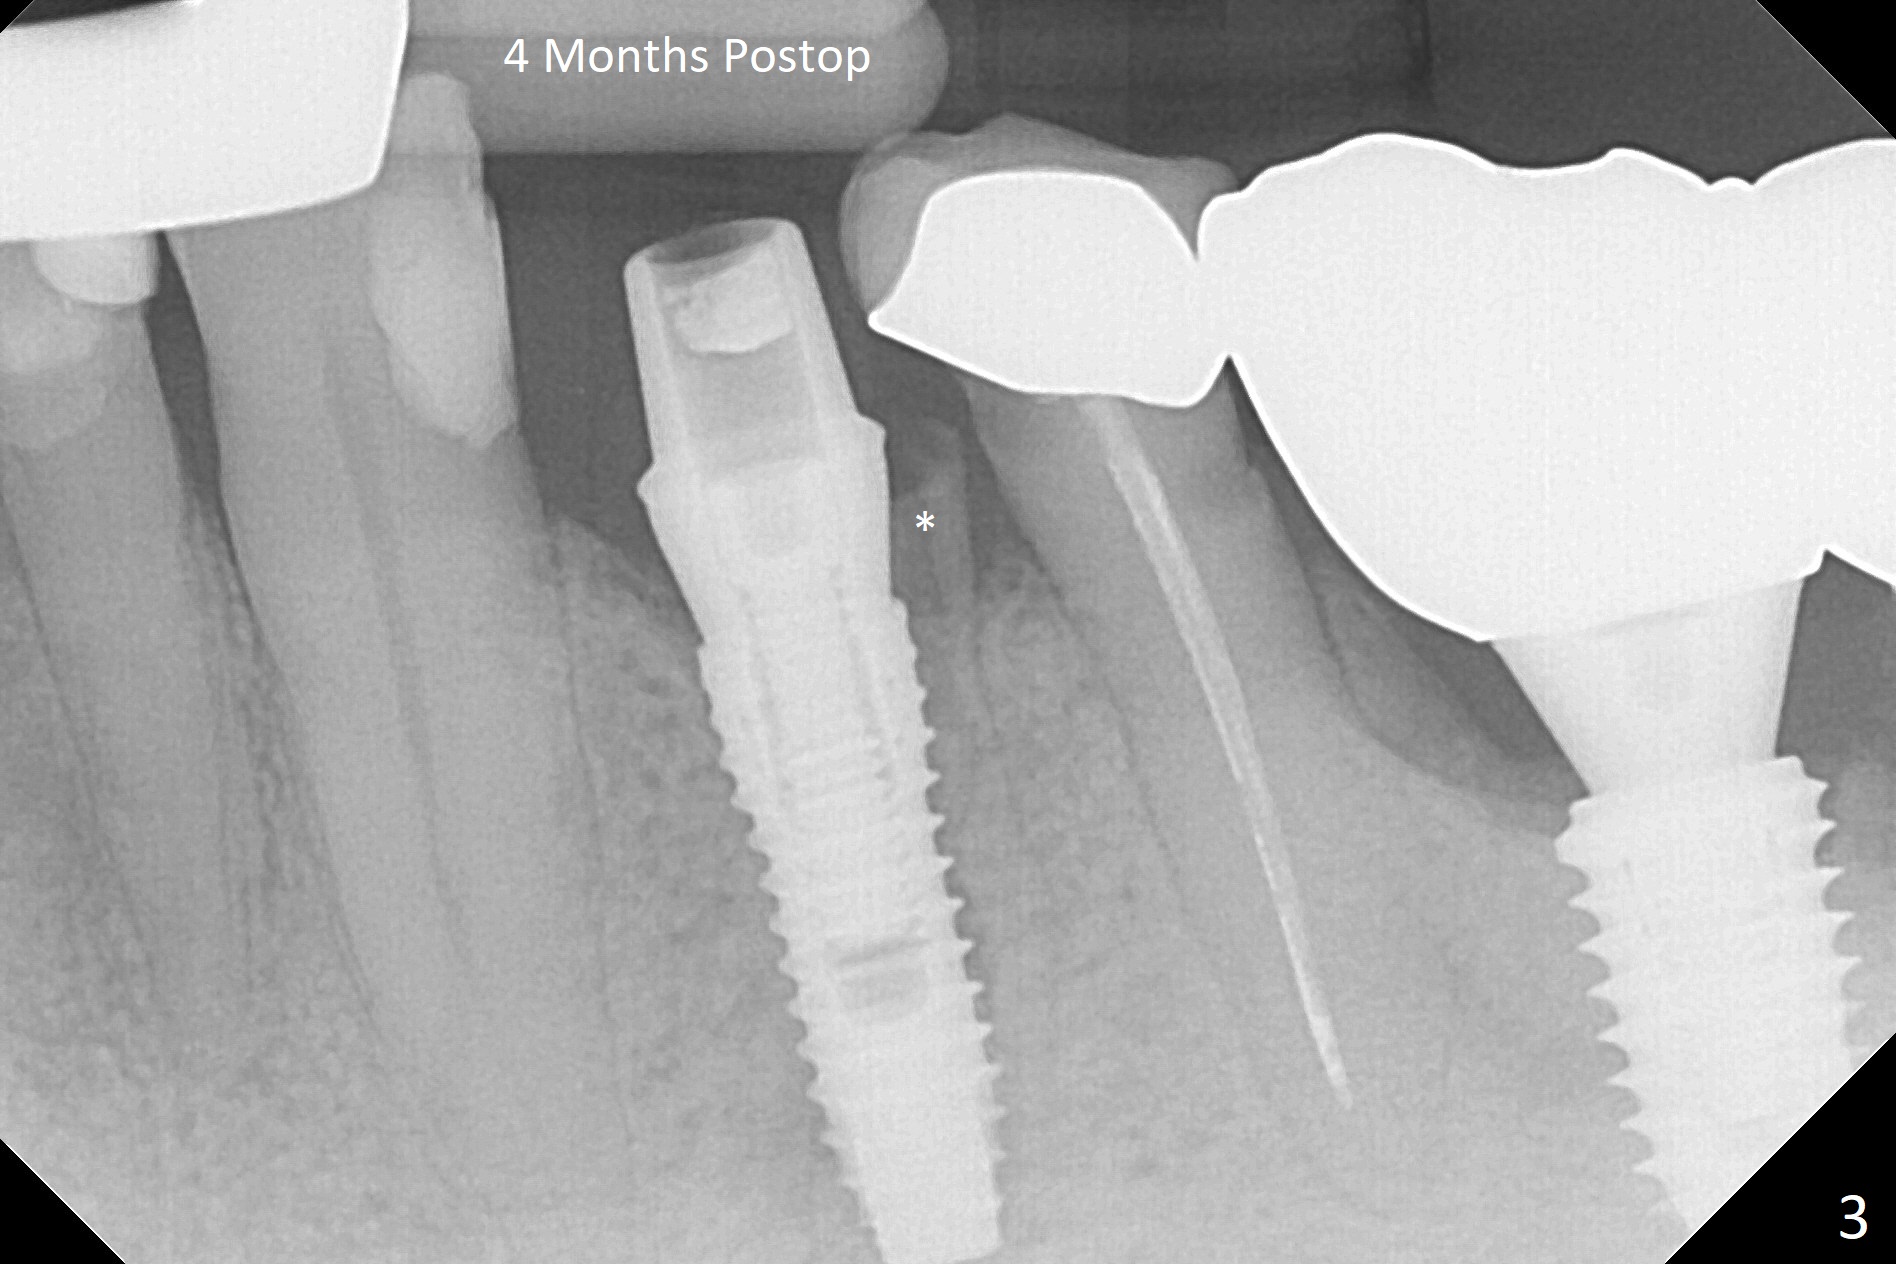

Extraction of the fractured tooth at #21 is as difficult as #19 (requiring incision). Because of the long root and hemorrhage, the apex of the tooth (Fig.1 black *) and a thin layer of the buccal shield (white *) remain when osteotomy is initiated. Due to hard bone, a 3.8x11.5 mm implant achieves insertion torque of ~35 Ncm (Fig.2); with placement of a 4.5x4(3) mm abutment, an immediate provisional is fabricated. There is limited remaining space for bone graft. The patient will return for final restoration 4 months postop; the buccal plate will be expected to have not collapsed! The implant seems to be osteointegrated, while the root piece (socket shield *) is exposed 4 months postop (Fig.3). The socket shield seems to be harmless, difficult to trim without local anesthesia and associated with no buccal plate concavity (Fig.4,5 <). With socket shield at #21, the crown looks normal, whereas the one at #19 without socket shield looks long, suggesting vertical bone loss early postop (before restoration, Fig.6).没有牙根处,角化龈少(图七,与术前(图八)对比)。